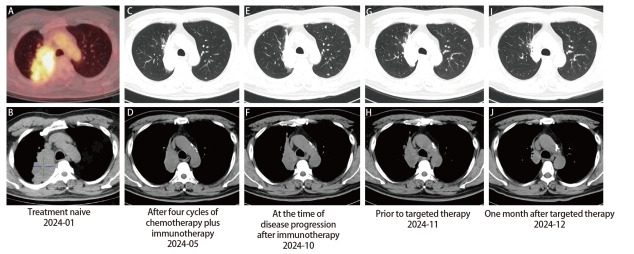

Epidermal growth factor receptor (EGFR) exon 20 mutations represent a rare subset of genetic alterations in non-small cell lung cancer (NSCLC). Among them, the complex mutation H773_V774delinsLM is exceedingly uncommon, accounting for only 0.2%-1% of all EGFR mutations. It is currently believed that rare EGFR mutations are generally resistant to the first- and second-generation EGFR-tyrosine kinase inhibitors (EGFR-TKIs). Although the third-generation EGFR-TKIs have shown some efficacy in certain rare mutations, clinical evidence regarding their use in NSCLC patients with the H773_V774delinsLM mutation remains sparse, and their efficacy and safety are yet to be clarified. Here, we present the first documented case of a patient with EGFR H773_V774delinsLM-mutant lung adenocarcinoma who experienced remarkable tumor regression following treatment with furmonertinib. This case highlights the potential utility of furmonertinib in treating patients with this rare EGFR mutation and may provide valuable insight into emerging treatment strategies for similarly affected patients.